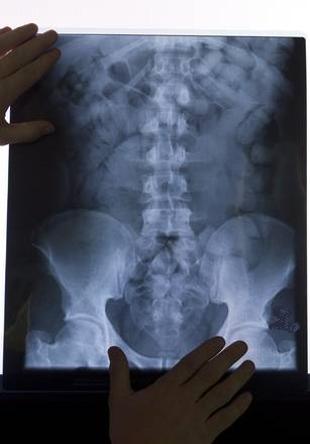

Osteoporosi: ogni 3 secondi un femore rotto a causa della malattia

In Italia circa 3,5 milioni di donne e 1 milione di uomini sono affetti dalla patologia

Le alterazioni macro e microarchitetturali che caratterizzano l’osteoporosi conducono ad una perdita progressiva delle proprietà biomeccaniche del tessuto osseo, con un conseguente aumento del rischio di caduta e di frattura. Le fratture da fragilità rappresentano, infatti, il drammatico epilogo della storia naturale dell’osteoporosi nell’anziano”.